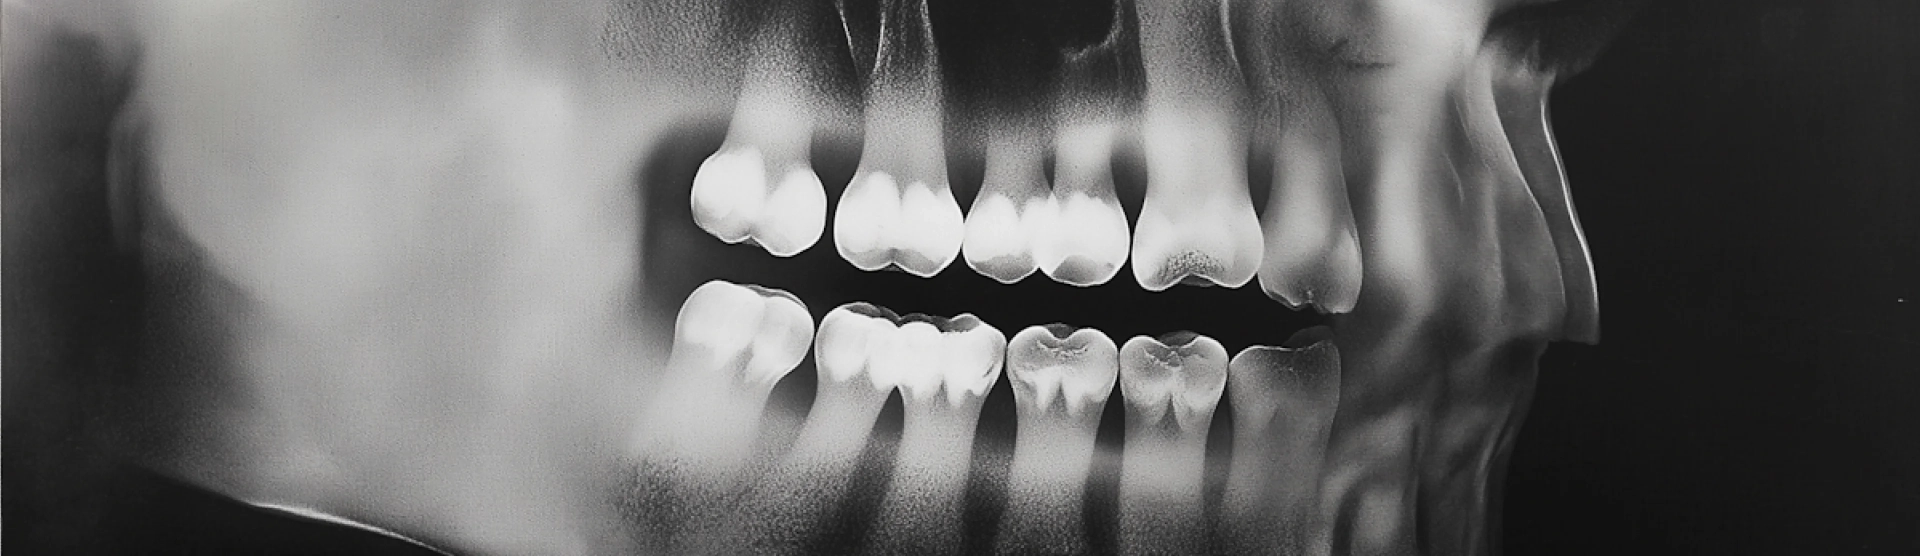

Dental Treatments: A Guide to Oral Health